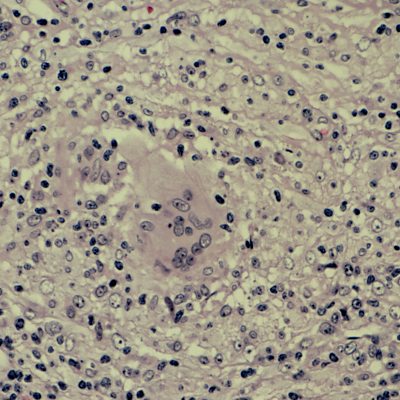

In the week that the US Centers for Disease Control and Prevention said that leprosy could now be endemic in the South-eastern United States, Claudia Hammond looks at global action on leprosy with science journalist Kamala Thiagarajan. There is an international effort to learn more about weaning seriously ill people off ventilator support in hospitals. We hear about the Weansafe study from Ireland. Professor of integrated community child health at University College London, Monica Lakhanpaul joins Claudia in the studio to discuss why the roll out of a new vaccine for RSV (Respiratory Syncytial Virus) in the US could be a gamechanger. And why on your next trip to a hospital, you could see groups of elderly in-patients going on walks. Could it help prevent the effects of bedrest? Image: Leprosy, nerve biopsy, nerve fibres surrounded by histiocytes Presenter: Claudia Hammond Producer: Clare Salisbury